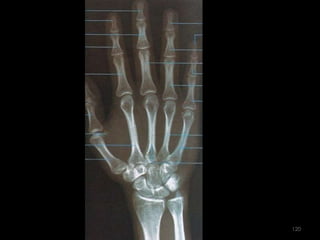

Incidência PA Mão118

119

120